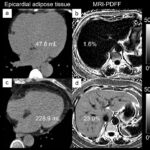

Liver fat and fibrosis are biomarkers of cardio-vascular risk in patients with diabetes mellitus

With the increased prevalence of metabolic syndrome, imaging now plays an additional prognostic role, especially in the personalization of cardio-vascular events. This paper prospectively shows the importance of liver disease and its relationship with...